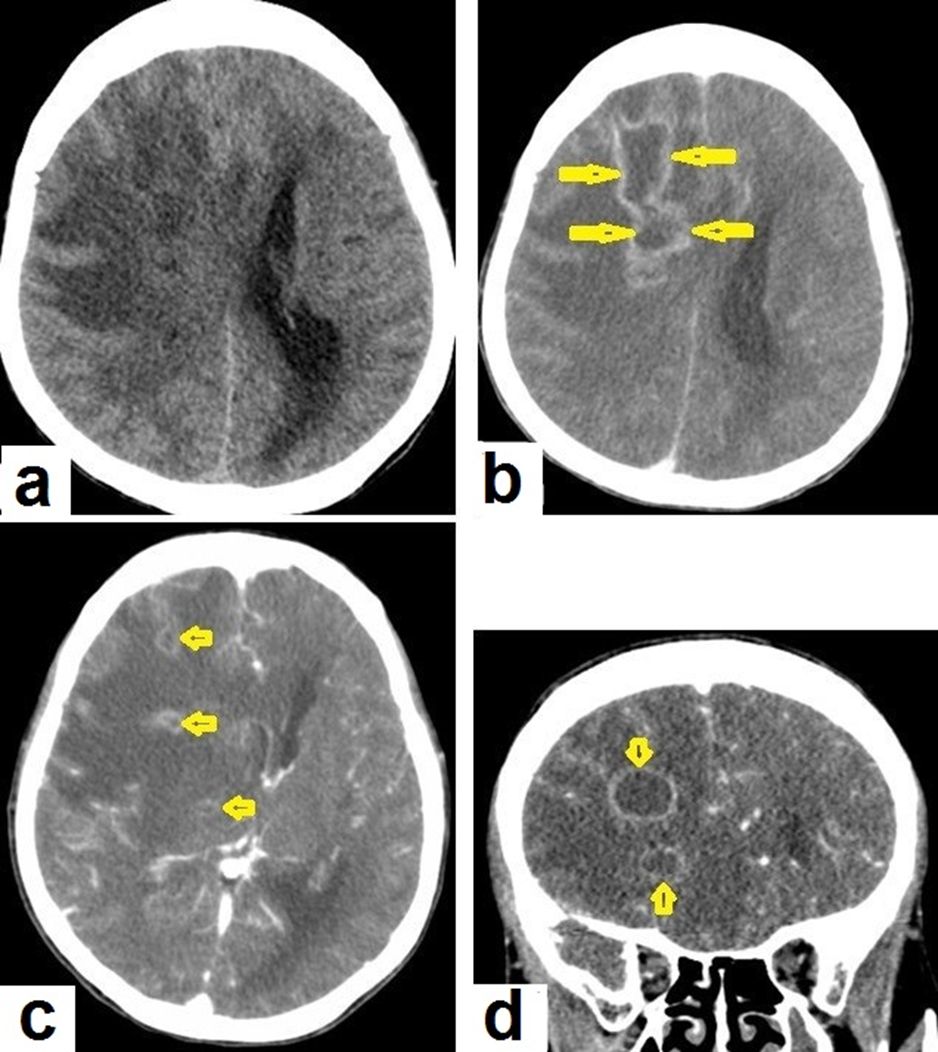

Figure 15. Tuberculous abscesses and tuberculomas in a 70-year-old woman with disturbance of consciousness and long history of headache. Selected axial computed tomography (CT) images of the brain (a) axial non-enhanced CT show significant vasogenic edema in the frontal and parietal lobes of the right cerebral hemisphere, with severe mass effect manifested as loss of the cortical sulci, total effacement of the right lateral ventricle and mild midline shift to the left side. (b) Contrast-enhanced CT (CECT) shows loculated rim-enhancing lesion centered in the right frontal lobe measures about 39 × 16 × 12 mm, suggesting cerebral abscess (arrows). (c) Axial CECT shows multiple ring-enhancing lesions in the right cerebral hemispheres and right basal ganglia (short arrows) suggesting of cerebral abscesses or tuberculomas. (d) Coronal CECT shows multiple ring-enhancing lesions in the right cerebral hemispheres (short arrows), suggesting cerebral tuberculomas or abscesses.